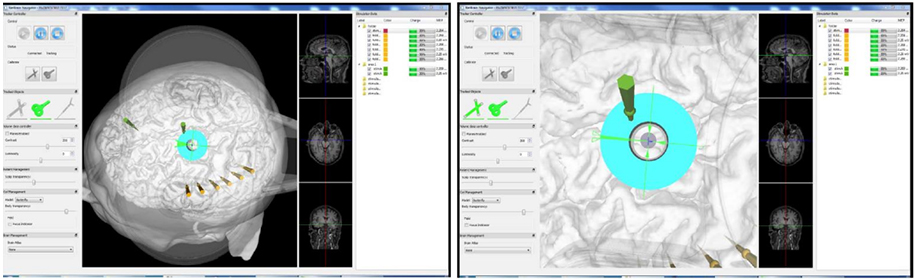

Quickly Calibrate Coils and Head Models

Use the pointer tool to select the position of the fixed reference point of the head and the reference point marked on the coil in turn to complete the coil calibration and head model configuration.

Visual editing tools to display stimulus target in 3D, set transparency

3D calibration for fast and easy proofreading

Present of the Stimulus Target in 3D

Visualization of stimulus target, support color page in 3D scene to display stimulation target area, in order to highlight it to distinguish it from other brain areas.